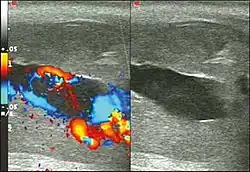

Ultrasonography

Penile ultrasonography with Doppler is the imaging method of choice, because it is noninvasive, widely available, and highly sensitive. By means of this method, it is possible to diagnose priapism and differentiate between its low- and high-flow forms.[11]

In low-flow (ischemic) priapism the flow in the cavernous arteries is reduced or absent. As the condition progresses, there is an increase in echogenicity of the corpora cavernosa, attributed to tissue edema. Eventually, changes in the echotexture of the corpora cavernosa can be observed due to the fibrotic transformation generated by tissue anoxia.[11]

In high-flow priapism normal or increased, turbulent blood flow in the cavernous arteries is seen. The area surrounding the fistula presents a hypoechoic, irregular lesion in the cavernous tissue.[11]